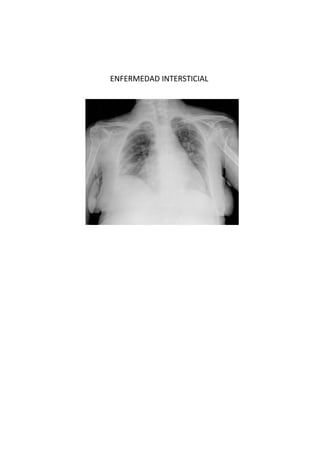

Este documento presenta 7 casos de patología torácica que serán discutidos en una sesión de interpretación radiológica. El objetivo es que los asistentes tomen notas aclaratorias durante la discusión interactiva de cada caso, en lugar de una mera explicación teórica. Los casos incluyen agenesia pulmonar derecha, situs inversus, estridor, neumonía con hemoptisis y enfermedad intersticial. El último caso involucra a un paciente de 86 años con tos y disnea que podría tener una consolidación en la base